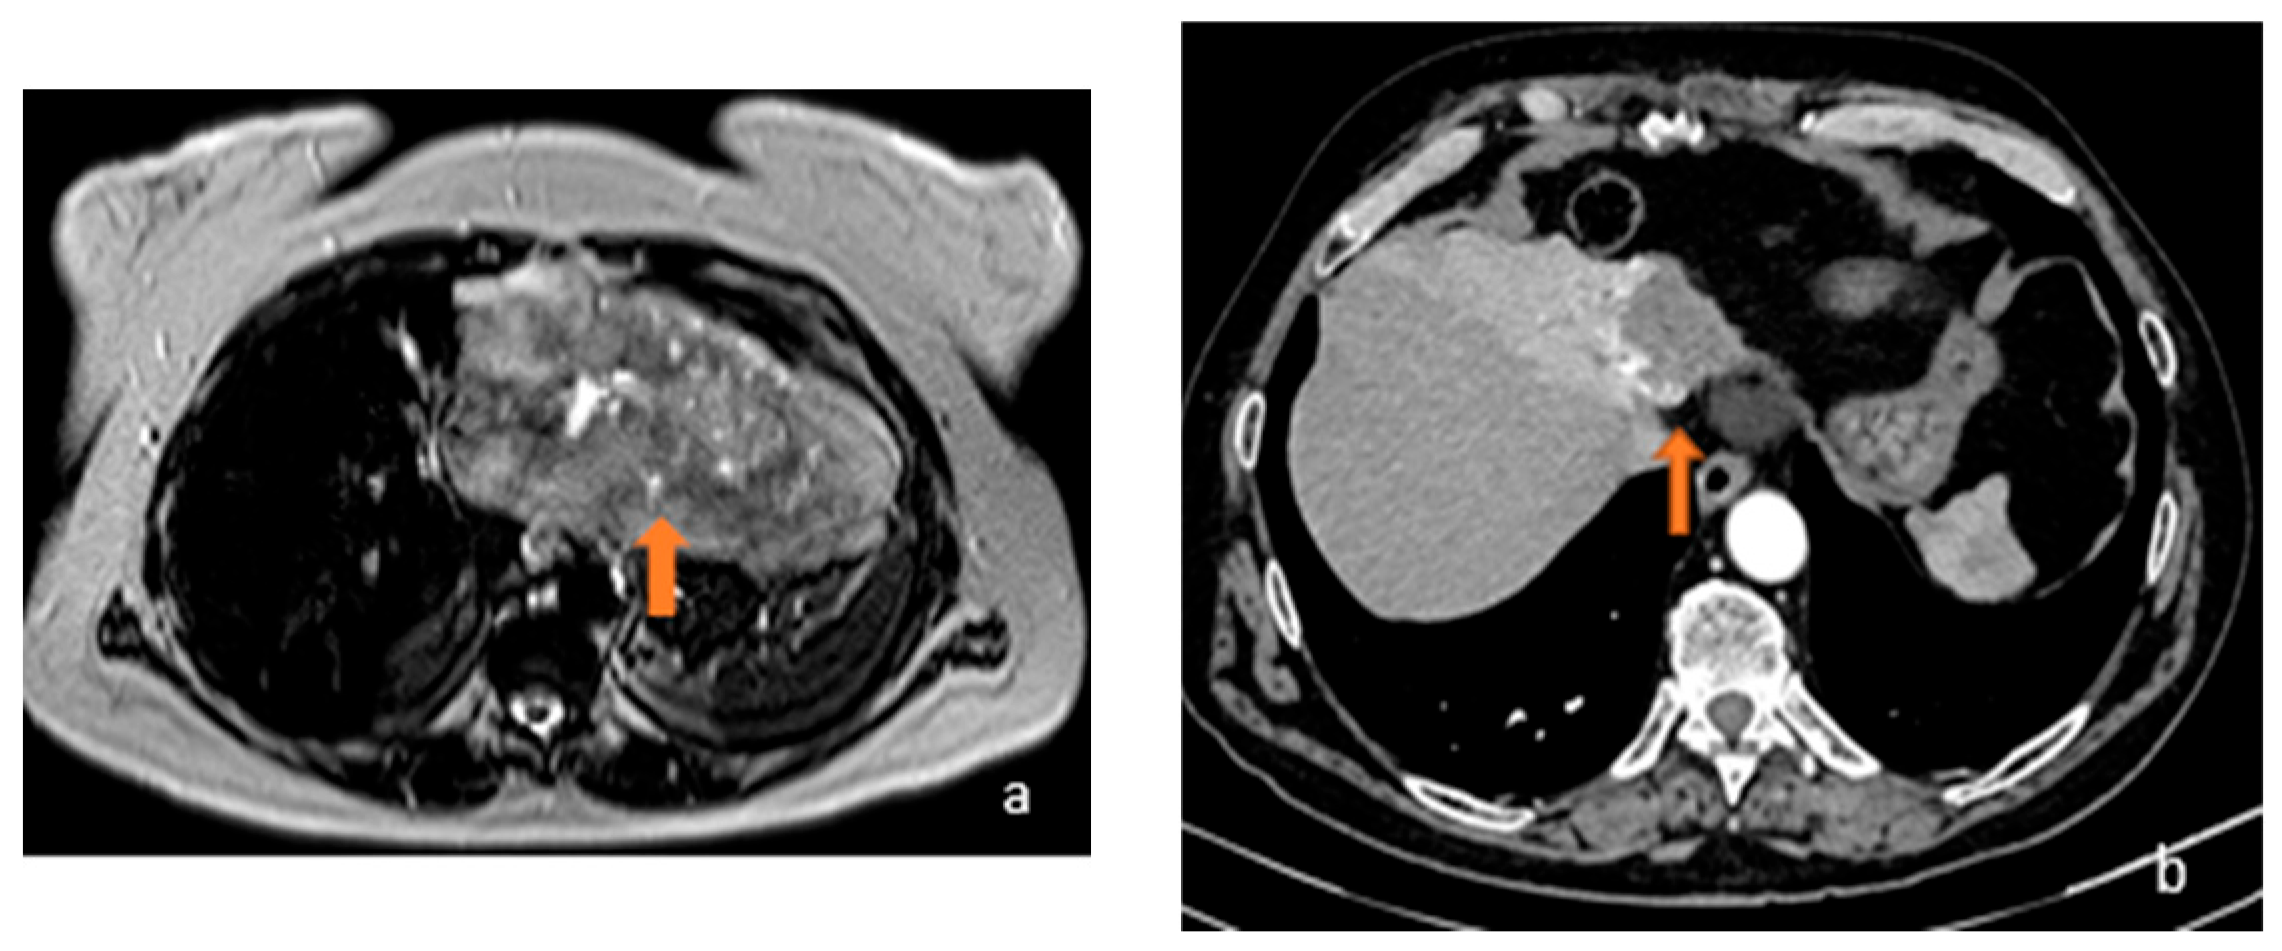

3.1. FLL Feature Characteristic

5.1. FLL Feature Characteristic

5.2. LFF MRI Radiomic Features OS and Response to Therapy